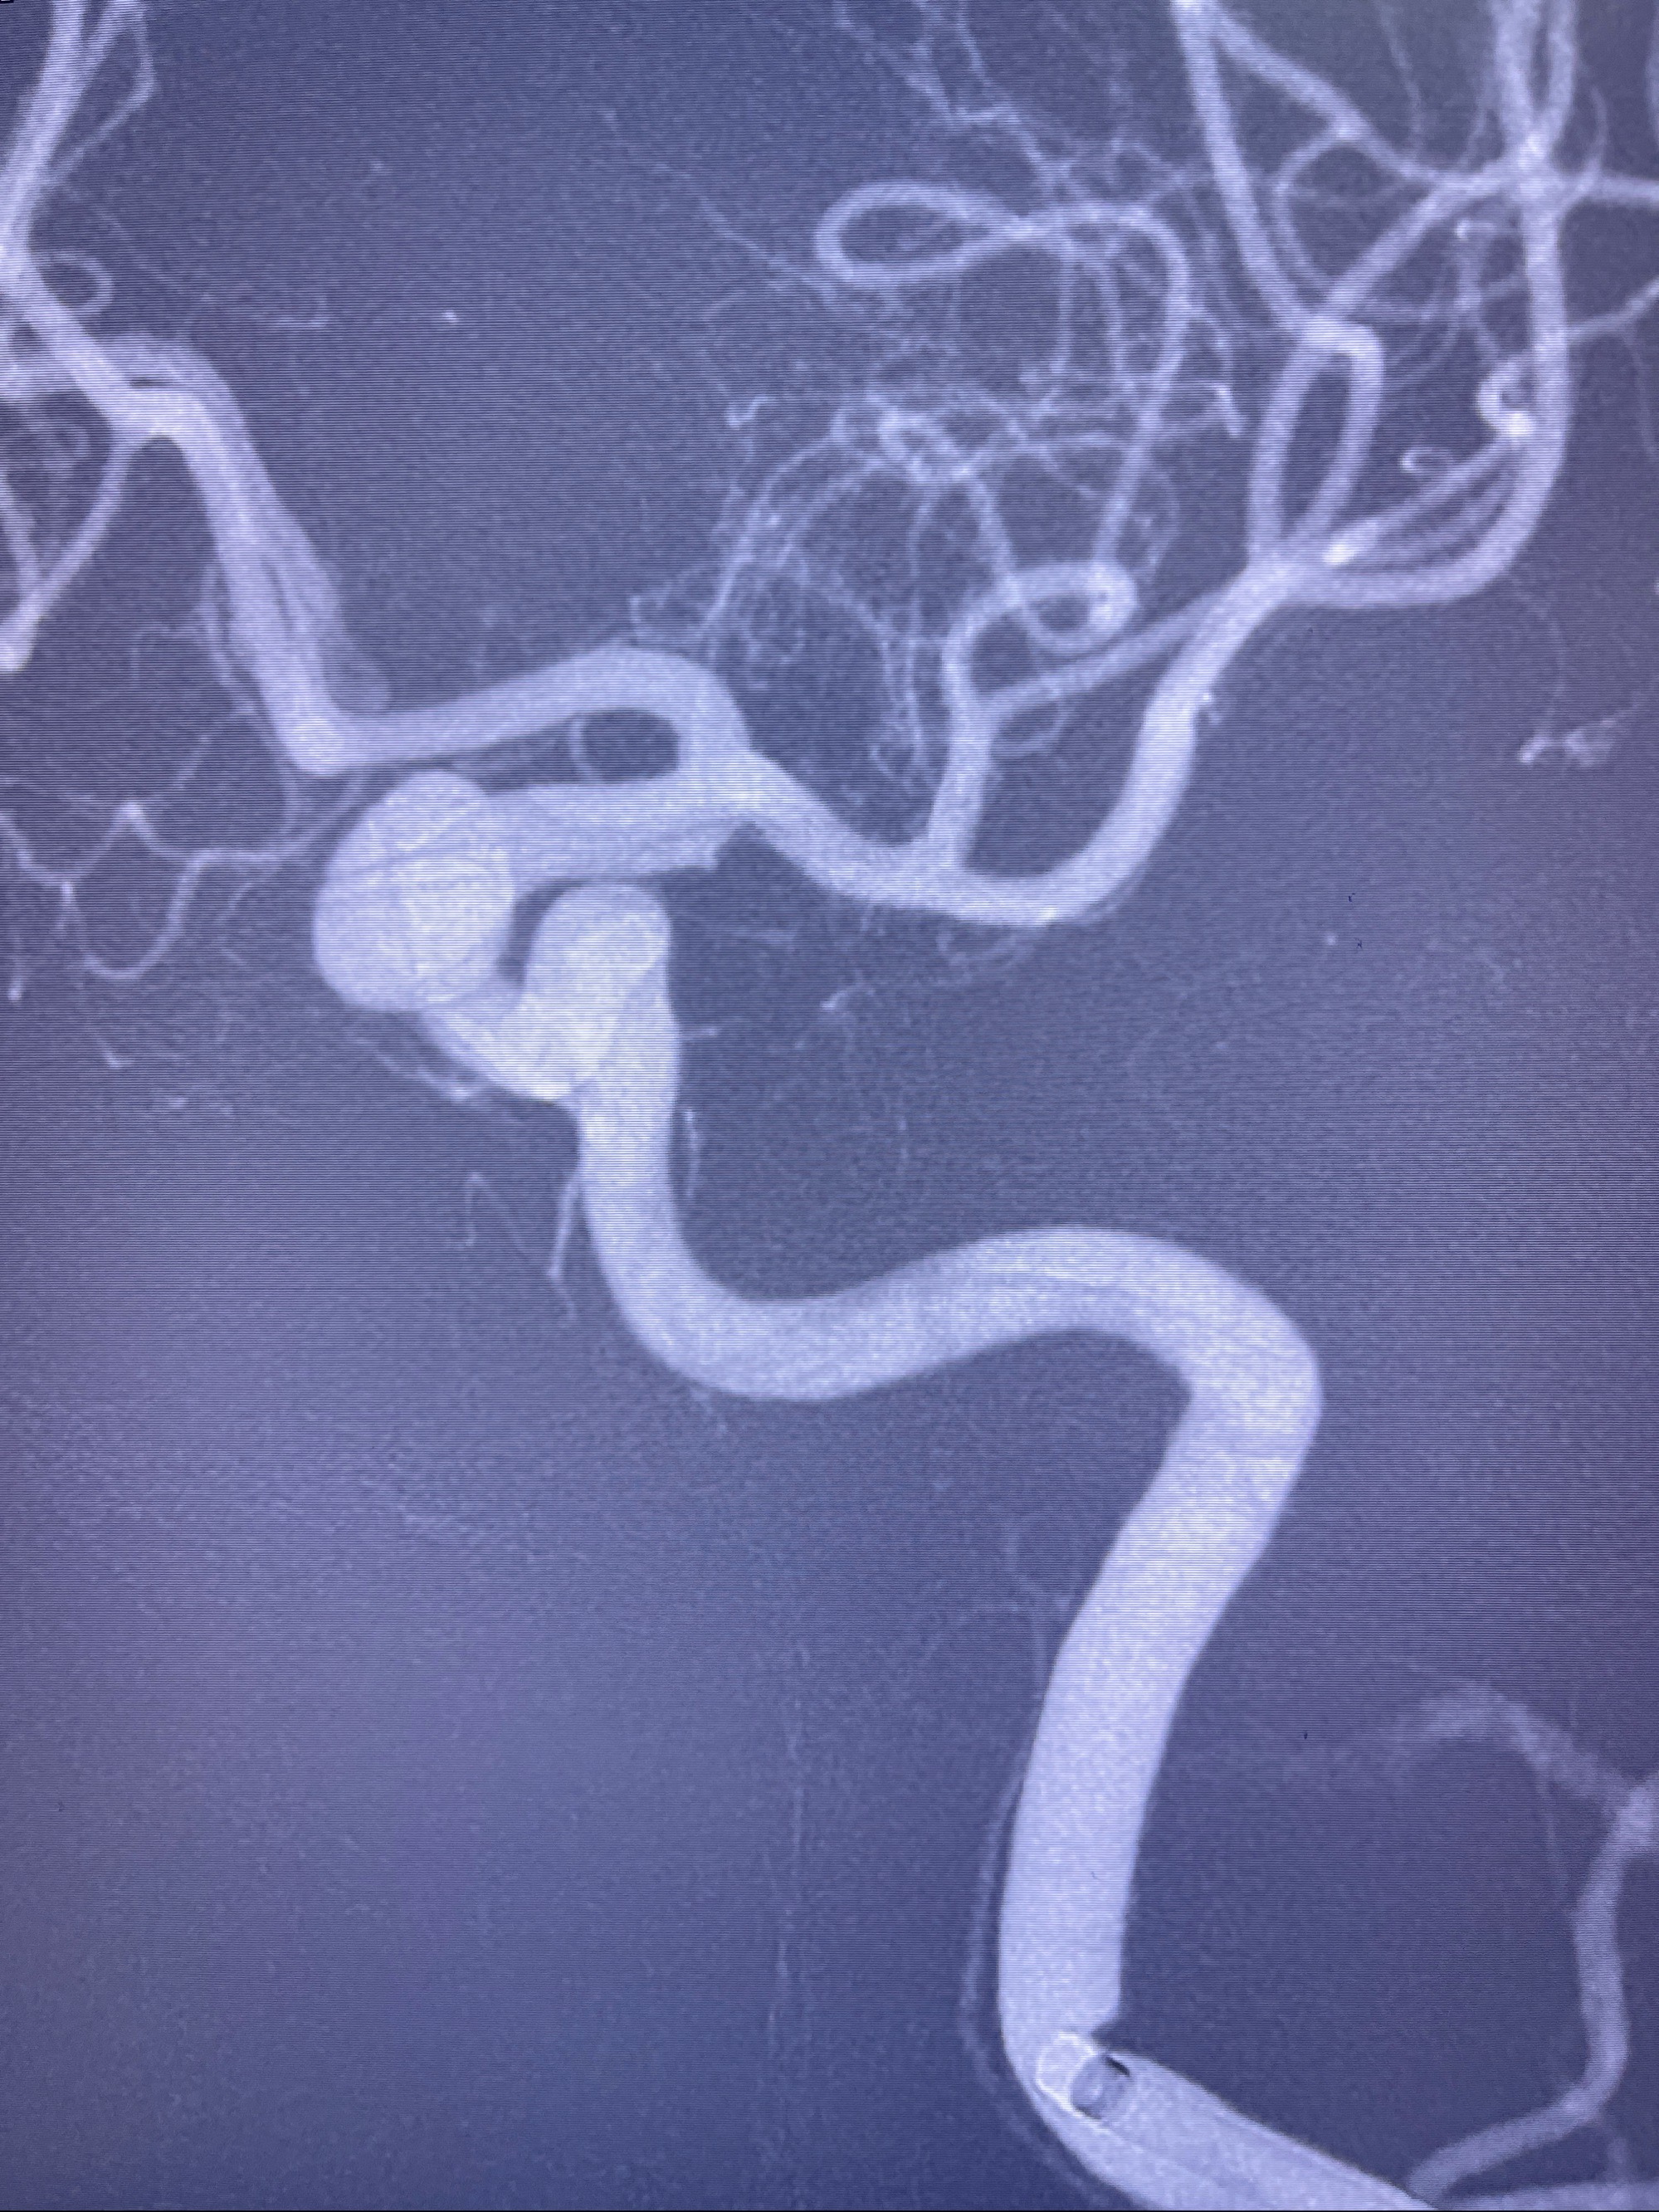

2023-08-30DSA:左侧颈内动脉眼动脉动脉瘤,约3*9.2*7.3mm大小

术后3D显示支架贴壁佳